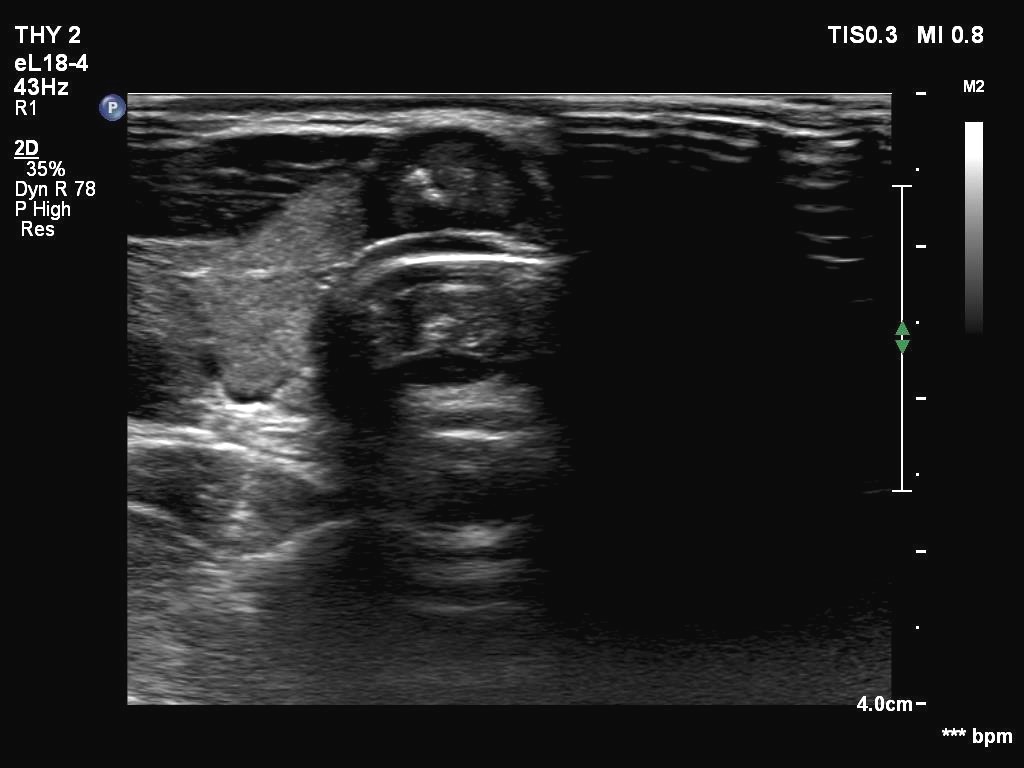

Ultrasonography. The thyroid was echonormal. There were two partly deeply hypoechoic nodules, one in the ventrolateral part of the right lobe and another one in the isthmus. Both had irregular margins and punctate echogenic foci. There was a mirror image artifact of the lesion in the isthmus.

According to the literature, the mirror image artifact is not an exceptional finding. Nevertheless, such a reflection very similar to the original is quite rare. The prerequisite of this phenomenon is the flattening of the trachea' wall as is observed in this case. The explanation is as follows: 'The primary beam reflects from such a surface (e.g. diaphragm) but instead of directly being received by the transducer, it encounters another structure (e.g. a nodular lesion) in its path and is reflected back to the highly reflective surface (e.g. diaphragm). It then again reflects back towards the transducer.' (Source: radiopedia.org.)